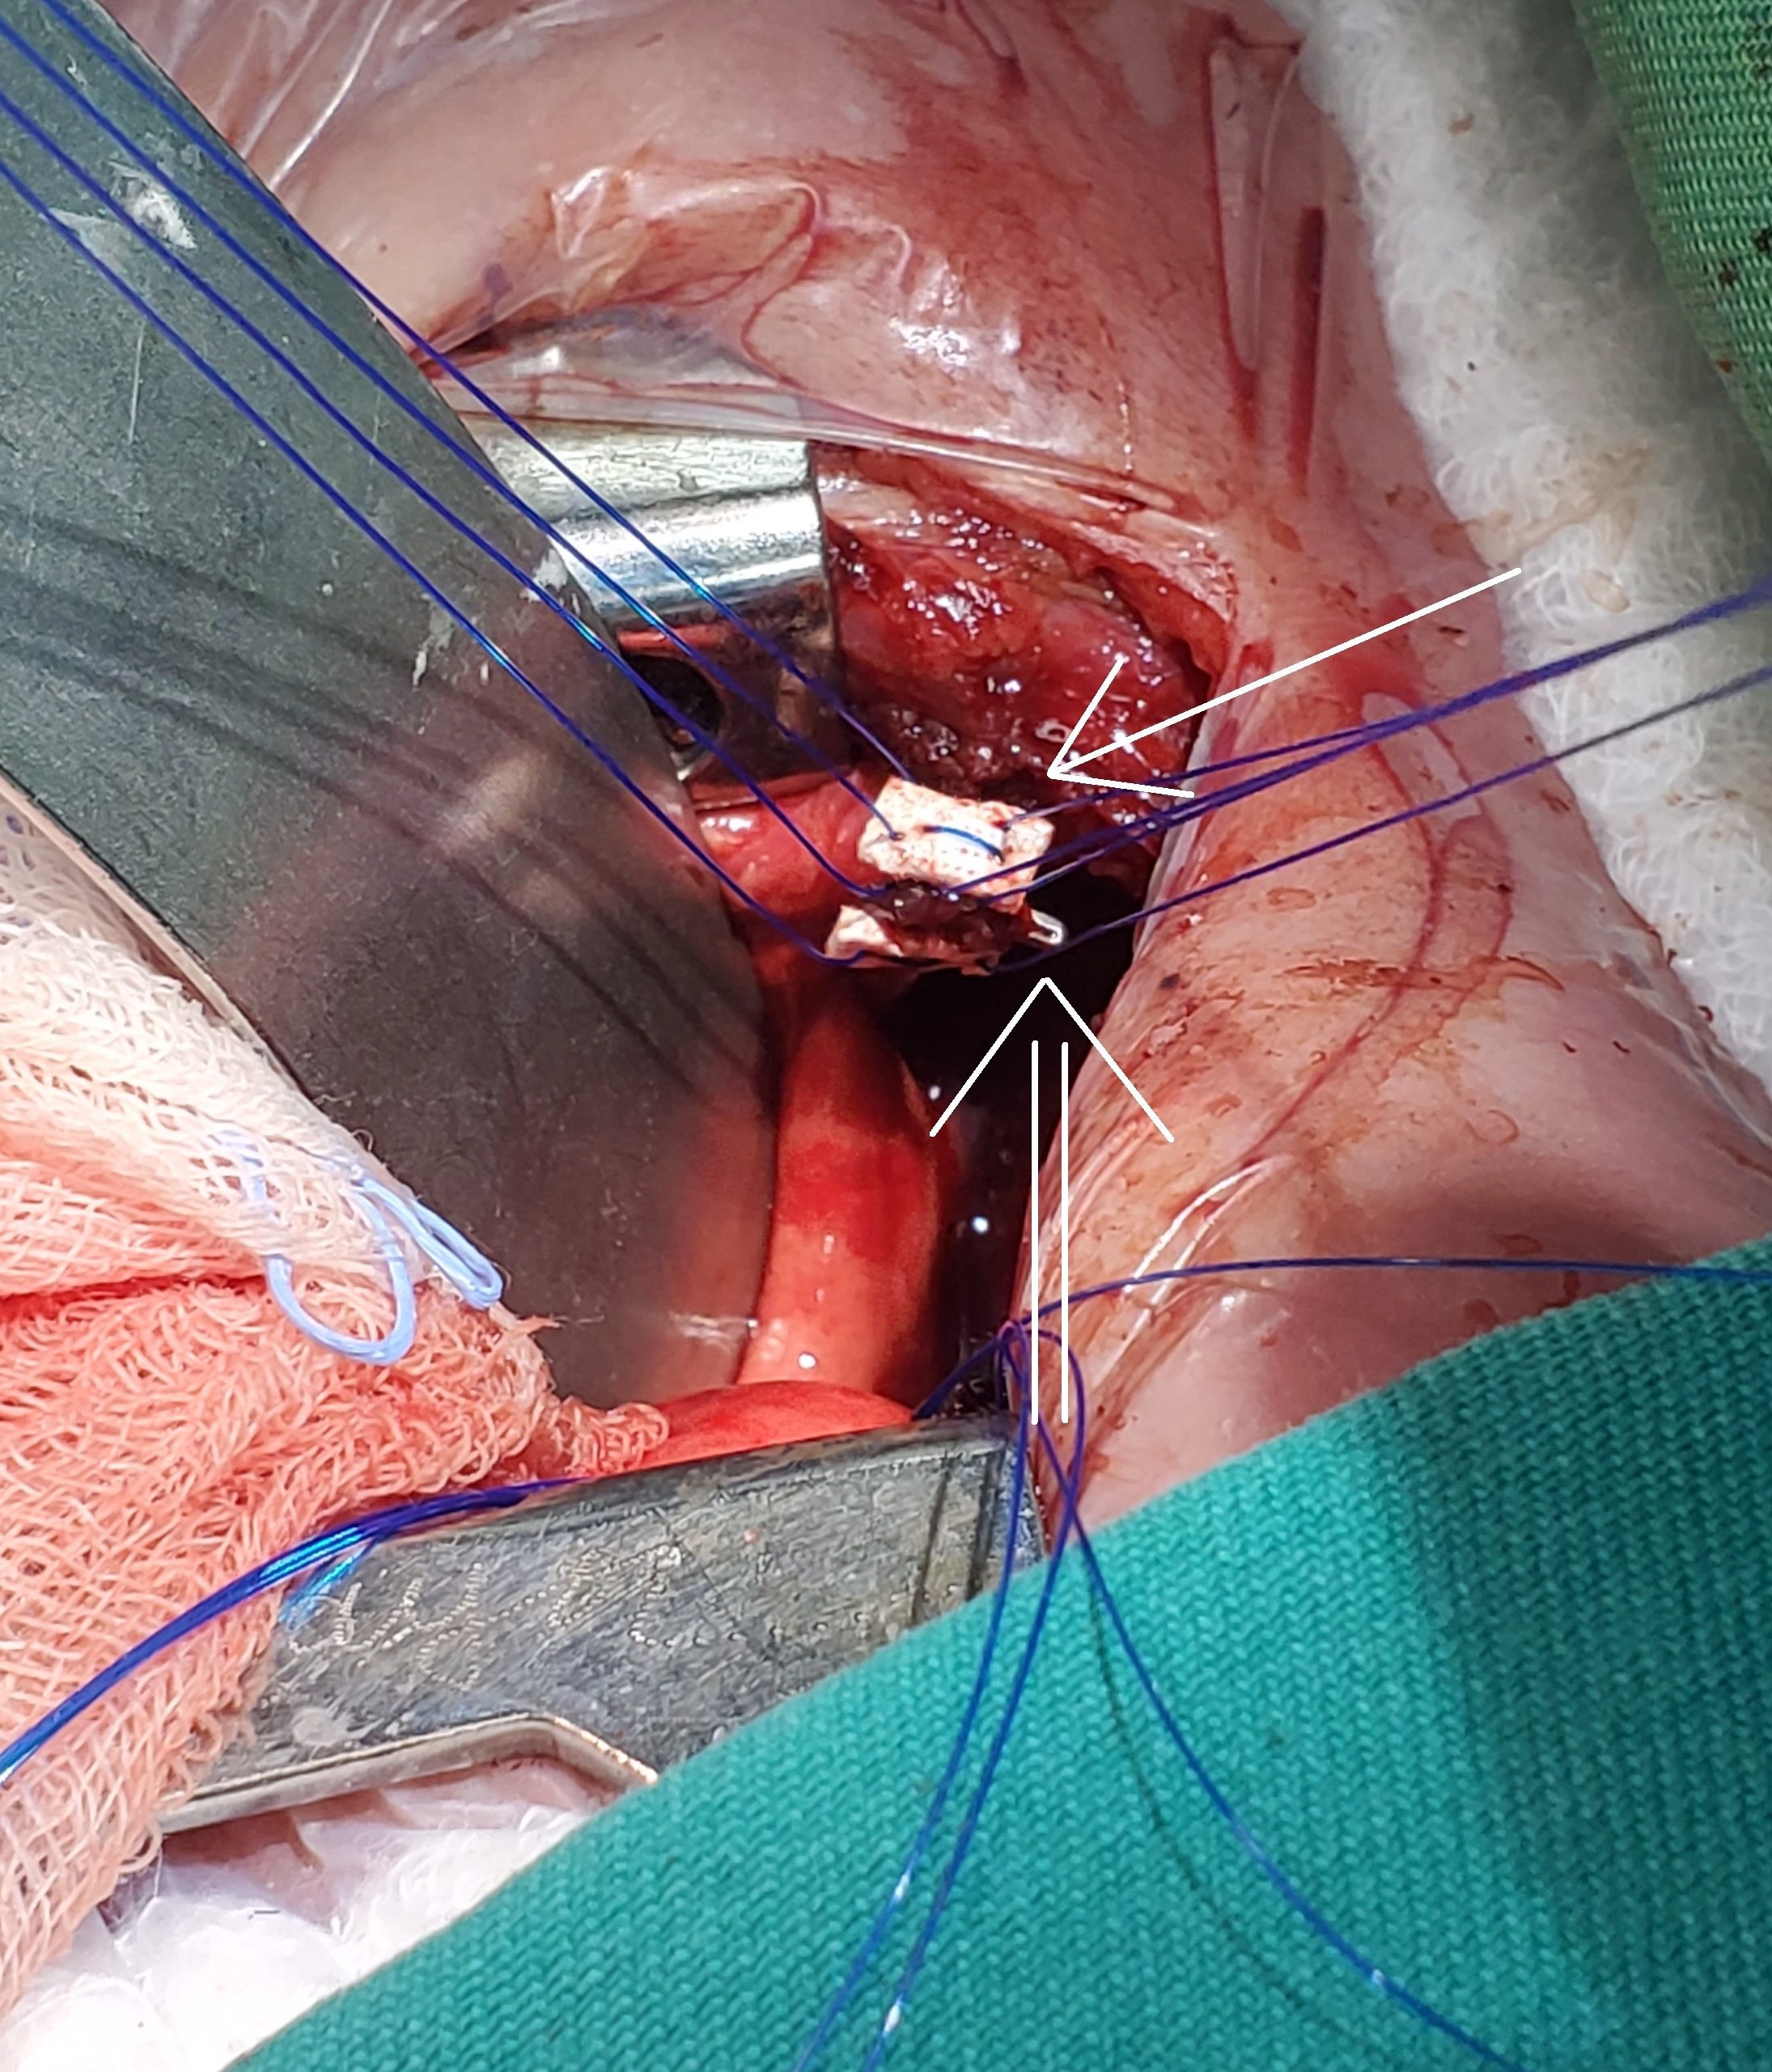

Technique: In the first step of the procedure, we mobilized the proximal and distal esophageal segments and placed pledgets on their ends. We then inserted prolene sutures through the full thickness of the esophagus, and reinforced it with a titanium clip (Fig. 1). The long ends of the sutures were externalized through the chest wall for traction. After 5 days, we began the esophageal elongation process at the bedside by gradually placing several segments of feeding tubes under the sutures (Fig. 2). We monitored the progress of esophageal lengthening with chest x-rays, using the titanium clips as a guide for the esophageal ends (Fig. 3). Once the distance between the esophageal segments was approximately the length of a vertebral body, we restored the esophageal continuity.

Figure 1

Traction suture for Foker Technique. We used a pledget suture (one line arrow) reinforced with a titanium clip (Two lines arrow).